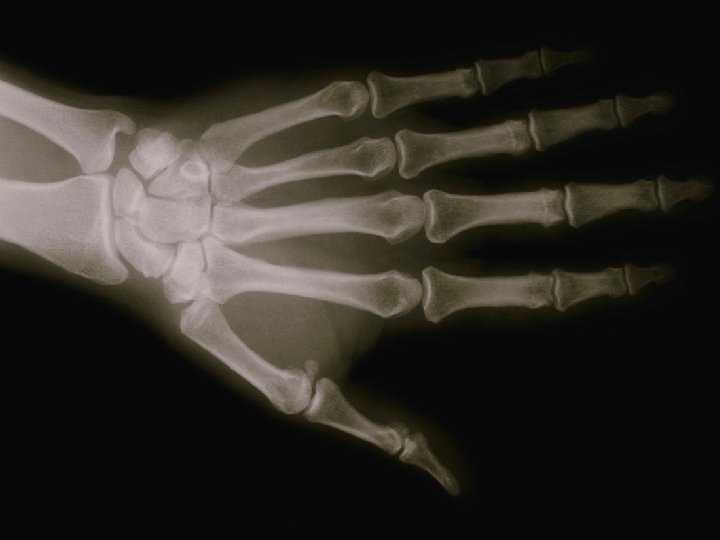

ORGANI ZA KRETANJE SU. . . Kostur i mišići tvore organe za kretanje. • Koja je najveća kost? • Koja je kost najmanja?

Odgovori brzo! • • • Organi su dijelovi organizma koji obavljaju određenu zadaću. DA NE Kosti su aktivni pokretači tijela. DA NE Najbolji su oni sportovi koji podjednako razvijaju sve mišiće. DA NE U sustav organa za pokretanje ubrajamo _______ i ______. Svojim se radom organi nadopunjavaju i čine skladnu cjelinu zvanu _______